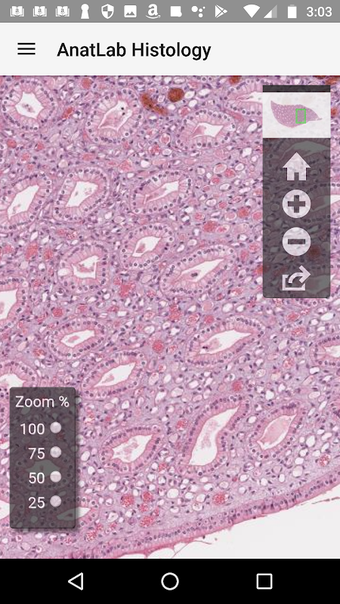

AnatLab Histology es una aplicación gratuita para Android desarrollada por Eolas Technologies Inc. que proporciona a los usuarios imágenes de diapositivas microscópicas de ultra alta resolución. Esta aplicación es una herramienta ideal para estudiantes, profesores, investigadores y el público en general. Con esta aplicación, pueden explorar el paisaje microscópico completo del cuerpo como si estuvieran mirando una colección de diapositivas reales en un microscopio físico. Tiene una función basada en la nube, la aplicación se puede acceder en cualquier dispositivo móvil Android, lo que la hace muy conveniente y accesible.

La aplicación ofrece una colección completa de imágenes de diapositivas microscópicas de histología que se pueden ver en ultra alta resolución. Las imágenes son de calidad excepcional y proporcionan una representación precisa del paisaje microscópico del cuerpo. La aplicación es fácil de usar y navegar, lo que permite a los usuarios explorar diferentes partes del cuerpo con facilidad.